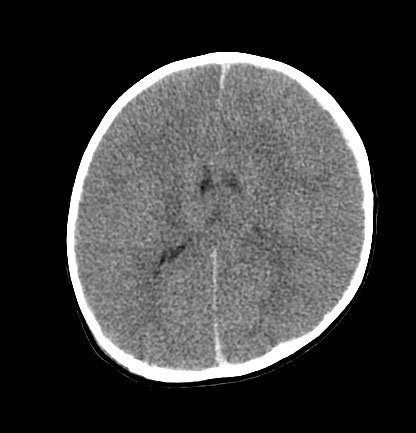

A neurosurgical consult is generally required in most cases of inflicted brain injury, especially when there are signs or symptoms of raised intracranial pressure such as irritability, vomiting, and a tense fontanelle, or radiological evidence.[Figure caption and citation for the preceding image starts]: CT scan revealing subdural haemorrhage extending over the right convexity and in the intrahemispheric region, as well as enlargement of the extra-axial fluid spacesFrom the personal collection of Alice Newton, MD; used with permission [Citation ends].